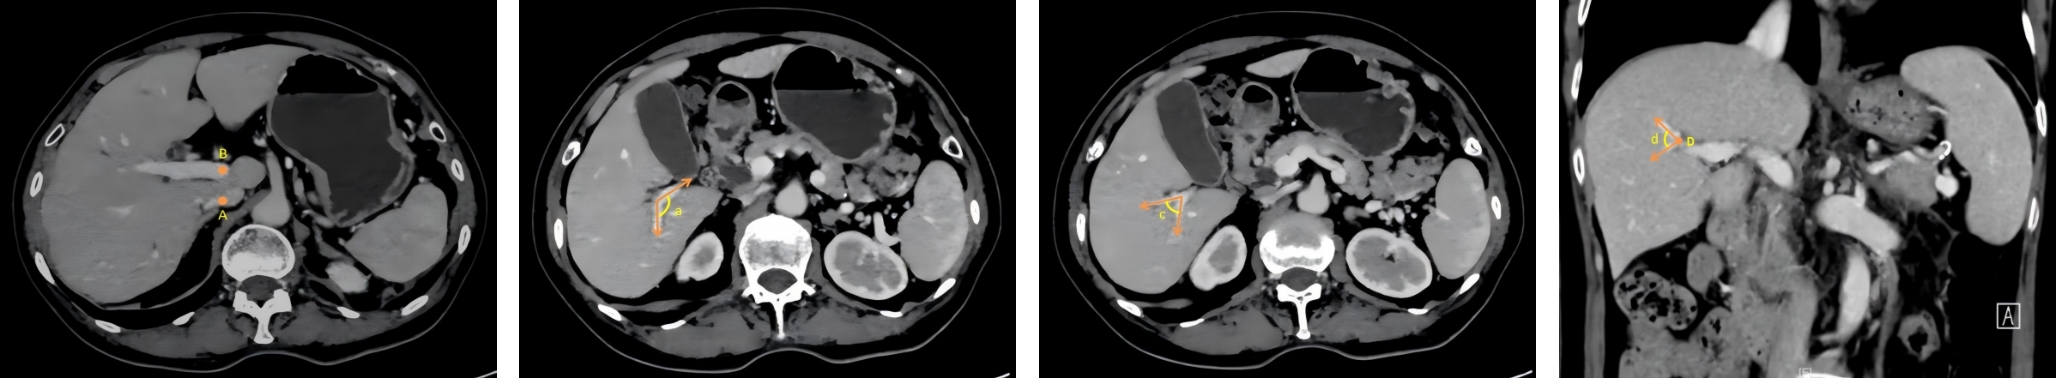

• Clinical application of three-dimensional visualization technology in assessing the spatial configuration of major hepatic vessels and liver lobar volume distribution

2026, 35(1):124-140. DOI: 10.7659/j.issn.1005-6947.250635

Abstract (93) HTML (137) PDF 3.82 M (171) Comment (0) Favorites

Abstract:Background and Aims The hepatic vascular and biliary systems exhibit substantial anatomical variability and complex spatial relationships, posing challenges for precise surgical planning based on conventional two-dimensional imaging. This study aimed to evaluate the clinical value of three-dimensional visualization in characterizing the spatial architecture of hepatic vasculature and bile ducts and to explore its association with hepatic volumetric distribution.Methods A total of 610 living liver donors and 158 patients with bile duct dilatation were retrospectively analyzed. Three-dimensional models of the hepatic artery, portal vein, hepatic veins, and bile ducts were reconstructed from contrast-enhanced CT images. Vascular and biliary anatomical patterns, spatial relationships, and their correlations with hepatic lobe and segmental volumes were systematically assessed.Results Three-dimensional visualization enabled intuitive and comprehensive depiction of hepatic vascular and biliary anatomy. Distinct portal vein configurations were associated with significant differences in regional liver volume distribution, with an increased proportion of the right posterior lobe observed in patients with specific portal vein branching patterns. The presence of an inferior right hepatic vein with a diameter ≥5 mm was also associated with a larger right posterior lobe volume. Analyses of extrahepatic and intrahepatic spatial relationships revealed relatively consistent positional patterns between the right hepatic artery, portal vein, and bile ducts, and a significant correlation was observed between the spatial courses of the right hepatic artery and the right posterior bile duct.Conclusion Three-dimensional visualization provides accurate preoperative assessment of hepatic vascular and biliary anatomy and clarifies complex spatial relationships and their volumetric implications. This technique offers critical anatomical support for precision hepatobiliary surgery and liver transplantation.